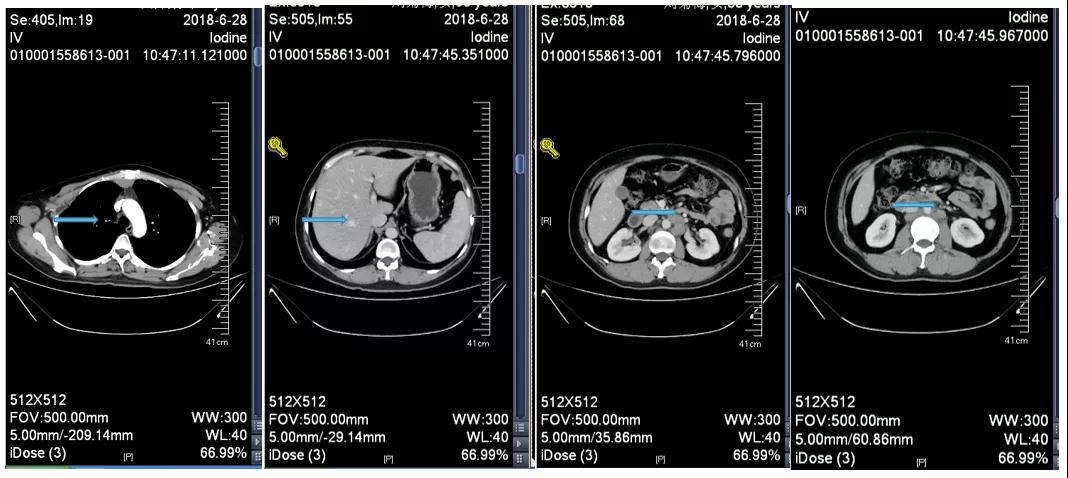

胸腹部增强CT示(2018-6-28):胸骨后占位,肝内异常强化灶,腹膜后肿大淋巴结。

诊断:右乳浸润性癌(rT2N3M1 IV期 HER2过表达型);卵巢转移瘤切除术后;腹膜后淋巴结转移;纵隔淋巴结转移;肝转移。

2018-7-17成功入组ELAINA临床研究(试验方案编号:BO29919),IWRS分配随机号3210。于2018-7-17开始接受T-DM1 3.6mg/kg(252mg)治疗,并间断对其进行疗效评估。现阶段患者PFS达近40个月。

靶病灶:腹主动脉左侧和下腔静脉右侧淋巴结

非靶病灶:肝左叶、肝右前叶下段;纵膈胸骨后淋巴结节;前上纵膈淋巴结;腹膜后小淋巴结